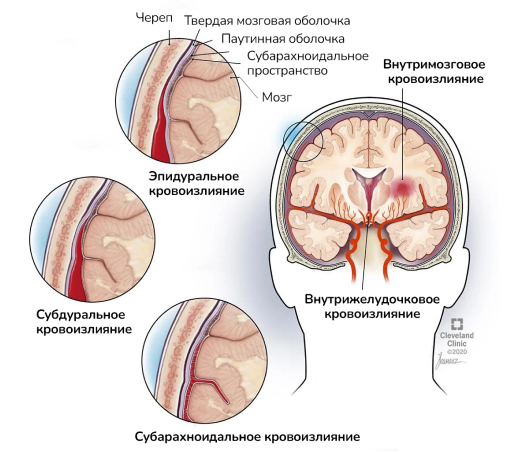

Хроническая ишемия головного мозга и лейкоареоз: симптомы и лечение